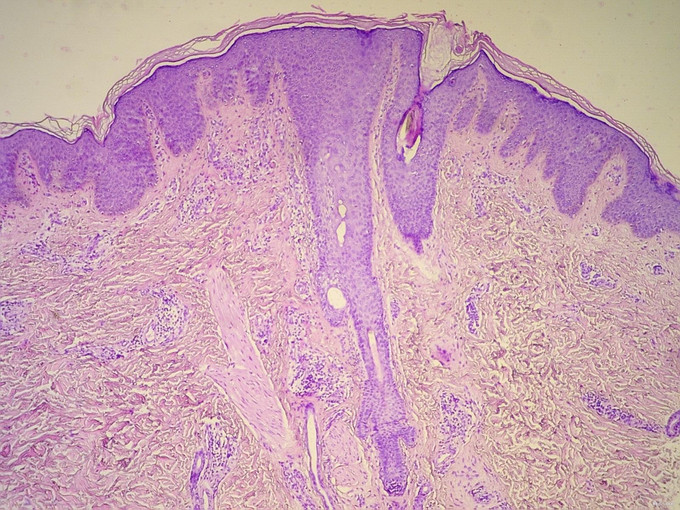

Fox-Fordyce病又称顶泌汗腺痒疹或顶泌汗腺毛囊角化病,最早由Fox和Fordyce报告。本病病因尚不完全清楚,可能在内分泌影响下,顶泌汗腺导管开口部位发生阻塞,导致顶泌汗腺分泌物潴留,顶泌汗腺导管破裂后,真皮内继发炎症反应而形成皮损。本病90%的患者发病于15岁~55岁的女性,偶可见于绝经后女性或男性。皮损仅发生在有顶泌汗腺部位的皮肤,主要为腋窝,其次为乳晕、脐窝、耻骨部及会阴部,分布对称。基本损害为针头至绿豆大小的毛囊性丘疹,质坚实,表面光滑,圆形,呈肤色或淡黄色,孤立散在,不融合。自觉剧痒,有的患者在月经期瘙痒加重。本病的组织学特点为毛囊壁海绵水肿性水疱,即顶泌汗腺潴留性水疱。毛囊漏斗部棘层肥厚,漏斗部周围的真皮中有炎性细胞浸润。 根据患儿的发病部位、皮疹形态再结合组织病理检查,不难诊断本病。本例特殊之处在于患者于青春期前发病,比较罕见。本病治疗困难。雌激素为最常有效的方法,通常采用口服避孕药。局部用维A酸、抗生素、外用或皮损内注射皮质激素,口服维A酸(异维A酸)及紫外线光疗对少数患者有效[3]。最近有作者使用1%吡美莫司治疗本病有效。